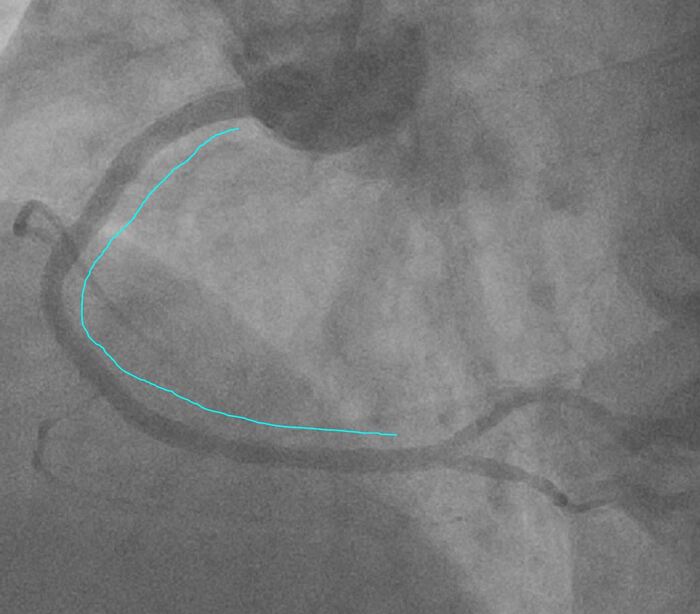

Возникла угроза полностью потерять сосуд, поэтому стентировали правую артерию на протяжении до устья с таким вот результатом:

Голубым обозначена зона стентирования.

Сразу скажу, чем больше стентов тем хуже отдаленный результат, из за повышенного риска рестеноза, тромбоза как раннего, так и позднего (full metal jacket делают не от "хорошей жизни" - как в этом случае).